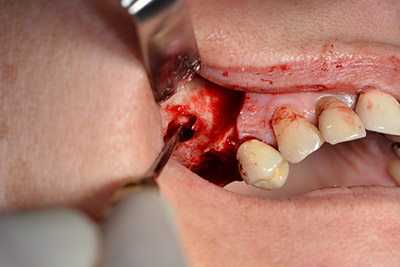

Etwa sechs Monate nach Extraktion der Zähne 16 und 14 wurde zur Planung und Risikominimierung eine digitale Volumentomografie (DVT, Planmeca) erstellt. Hierbei wurde deutlich, dass der Knochen sich nicht in der gewünschten Quantität regeneriert hat (Abb. 2 bis 7).

Abb. 2 bis 7: DVT mit stark reduziertem horizontalen Knochenangebot.

Um eine festsitzende Versorgung auf mindestens zwei Implantaten zu gewährleisten, ist eine Sinusbodenelevation sowohl in Regio 16 als auch in Regio 14 erforderlich. Da in diesem Fall das Restknochenangebot extrem gering ist, müsste ein verhältnismäßig großer Knochenaufbau durchgeführt werden. Große Knochenaufbauverfahren sind invasiv, mit einer höheren Patientenmorbidität verbunden, zeitintensiv und kostspielig. Die Vorhersagbarkeit der Behandlungsresultate ist geringer und das Misserfolgsrisiko höher. Vor dem Hintergrund dieser Nachteile, wurde die Patientin über eine herausnehmbare Alternative aufgeklärt, die sie jedoch konsequent ablehnte.

Um die Augmentation auf Regio 14 einzuschränken, wurde in Absprache mit der Patientin eine Schrägstellung des Implantats 16 nach dorso-kranial geplant (Abb. 8).